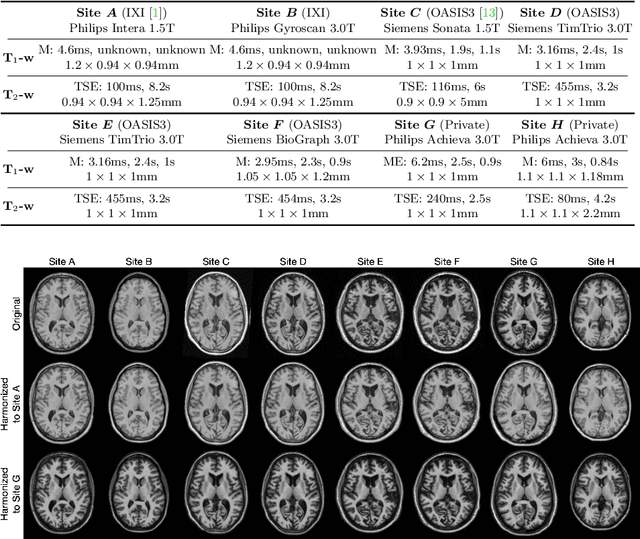

Abstract:Magnetic resonance (MR) imaging is commonly used in the clinical setting to non-invasively monitor the body. There exists a large variability in MR imaging due to differences in scanner hardware, software, and protocol design. Ideally, a processing algorithm should perform robustly to this variability, but that is not always the case in reality. This introduces a need for image harmonization to overcome issues of domain shift when performing downstream analysis such as segmentation. Most image harmonization models focus on acquisition parameters such as inversion time or repetition time, but they ignore an important aspect in MR imaging -- resolution. In this paper, we evaluate the impact of image resolution on harmonization using a pretrained harmonization algorithm. We simulate 2D acquisitions of various slice thicknesses and gaps from 3D acquired, 1mm3 isotropic MR images and demonstrate how the performance of a state-of-the-art image harmonization algorithm varies as resolution changes. We discuss the most ideal scenarios for image resolution including acquisition orientation when 3D imaging is not available, which is common for many clinical scanners. Our results show that harmonization on low-resolution images does not account for acquisition resolution and orientation variations. Super-resolution can be used to alleviate resolution variations but it is not always used. Our methodology can generalize to help evaluate the impact of image acquisition resolution for multiple tasks. Determining the limits of a pretrained algorithm is important when considering preprocessing steps and trust in the results.

Abstract:The lack of standardization is a prominent issue in magnetic resonance (MR) imaging. This often causes undesired contrast variations due to differences in hardware and acquisition parameters. In recent years, MR harmonization using image synthesis with disentanglement has been proposed to compensate for the undesired contrast variations. Despite the success of existing methods, we argue that three major improvements can be made. First, most existing methods are built upon the assumption that multi-contrast MR images of the same subject share the same anatomy. This assumption is questionable since different MR contrasts are specialized to highlight different anatomical features. Second, these methods often require a fixed set of MR contrasts for training (e.g., both Tw-weighted and T2-weighted images must be available), which limits their applicability. Third, existing methods generally are sensitive to imaging artifacts. In this paper, we present a novel approach, Harmonization with Attention-based Contrast, Anatomy, and Artifact Awareness (HACA3), to address these three issues. We first propose an anatomy fusion module that enables HACA3 to respect the anatomical differences between MR contrasts. HACA3 is also robust to imaging artifacts and can be trained and applied to any set of MR contrasts. Experiments show that HACA3 achieves state-of-the-art performance under multiple image quality metrics. We also demonstrate the applicability of HACA3 on downstream tasks with diverse MR datasets acquired from 21 sites with different field strengths, scanner platforms, and acquisition protocols.

Abstract:Accuracy and consistency are two key factors in computer-assisted magnetic resonance (MR) image analysis. However, contrast variation from site to site caused by lack of standardization in MR acquisition impedes consistent measurements. In recent years, image harmonization approaches have been proposed to compensate for contrast variation in MR images. Current harmonization approaches either require cross-site traveling subjects for supervised training or heavily rely on site-specific harmonization models to encourage harmonization accuracy. These requirements potentially limit the application of current harmonization methods in large-scale multi-site studies. In this work, we propose an unsupervised MR harmonization framework, CALAMITI (Contrast Anatomy Learning and Analysis for MR Intensity Translation and Integration), based on information bottleneck theory. CALAMITI learns a disentangled latent space using a unified structure for multi-site harmonization without the need for traveling subjects. Our model is also able to adapt itself to harmonize MR images from a new site with fine tuning solely on images from the new site. Both qualitative and quantitative results show that the proposed method achieves superior performance compared with other unsupervised harmonization approaches.